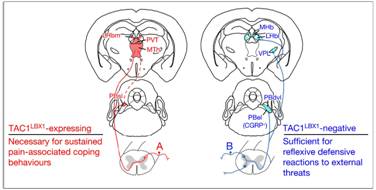

我们身体有两套感觉神经,支配我们人体皮肤的神经对切割、挤压、打击这种外力作用会感觉到明显的疼痛。

肠道深藏在腹腔内,基本不会遇到切割、挤压这种情况出现,所以胃肠道神经对切割挤压等外力作用没什么感觉。